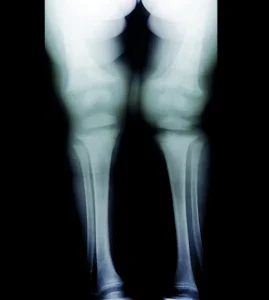

1. Kemik Deformasyonları

Raşitizm, kemiklerin normal şekilde sertleşmemesine ve büyümesine yol açar. Bu durum, uzun kemiklerde (bacaklar, kollarda) deformasyonlara neden olabilir. Bacaklar genellikle eğilebilir ve dizler birbirine yakınlaşabilir. Ayrıca, omurga eğriliği (skolyoz veya kifoz) gelişebilir.

3. Röntgen

Kemik deformasyonlarını tespit etmek için röntgen filmi çekilebilir. Röntgen, kemiklerin zayıflamasını ve deformasyonunu net bir şekilde gösterebilir.